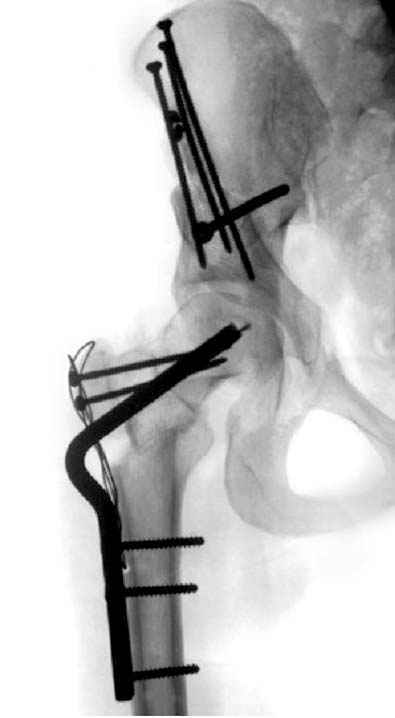

после операции при дисплазии тазобедренного

сустава #4

сустава #5

№ 4-6 после операции при дисплазии тазобедренного

сустава

№ 11-12 послеоперационные, с учетом биомеханики